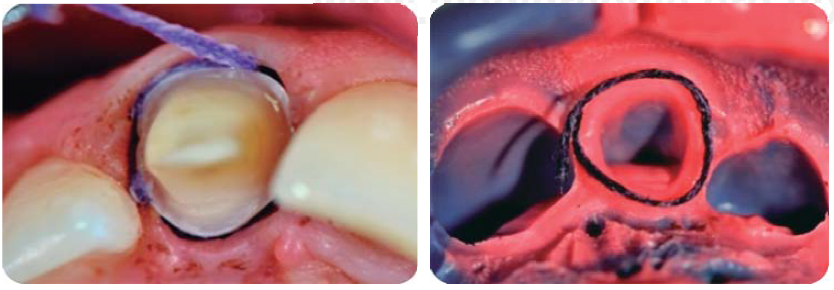

Alargamientos de coronas con fines endodónticos y restaurativos

Con una hoja de bisturí 15c, se realiza una incisión a bisel interno y luego una intrasurcal para eliminar un collar de encía y continuar levantando un colgajo de espesor total para exponer la estructura radicular remanente (Figura 8).

Se realizan las medidas con una sonda periodontal, para determinar la cantidad de tejido óseo que se debe eliminar con la osteotomía y osteoplastia para asegurar el efecto férula necesario para las restauraciones provisionales. Se mide con la sonda para asegurar una osteotomía de mínimo 3 mm (Figura 9), se procede a suturar con puntos simples (Figura 10).14

Preparación de muñón

Con la finalidad de restaurar con corona de disilicato de litio23 se toma la impresión con poliéter (Impregum Soft ® 3M) usando la técnica de separación gingival a doble hilo (Figura 22).24

Siendo extremadamente conservadores y con el objetivo de restaurar con corona de cerómero (SR Adoro, Ivoclar Vivadent), se toma la impresión con polivinilsiloxano de 3M (Express ®) usando la técnica de separación gingival a doble hilo (Figura 30).